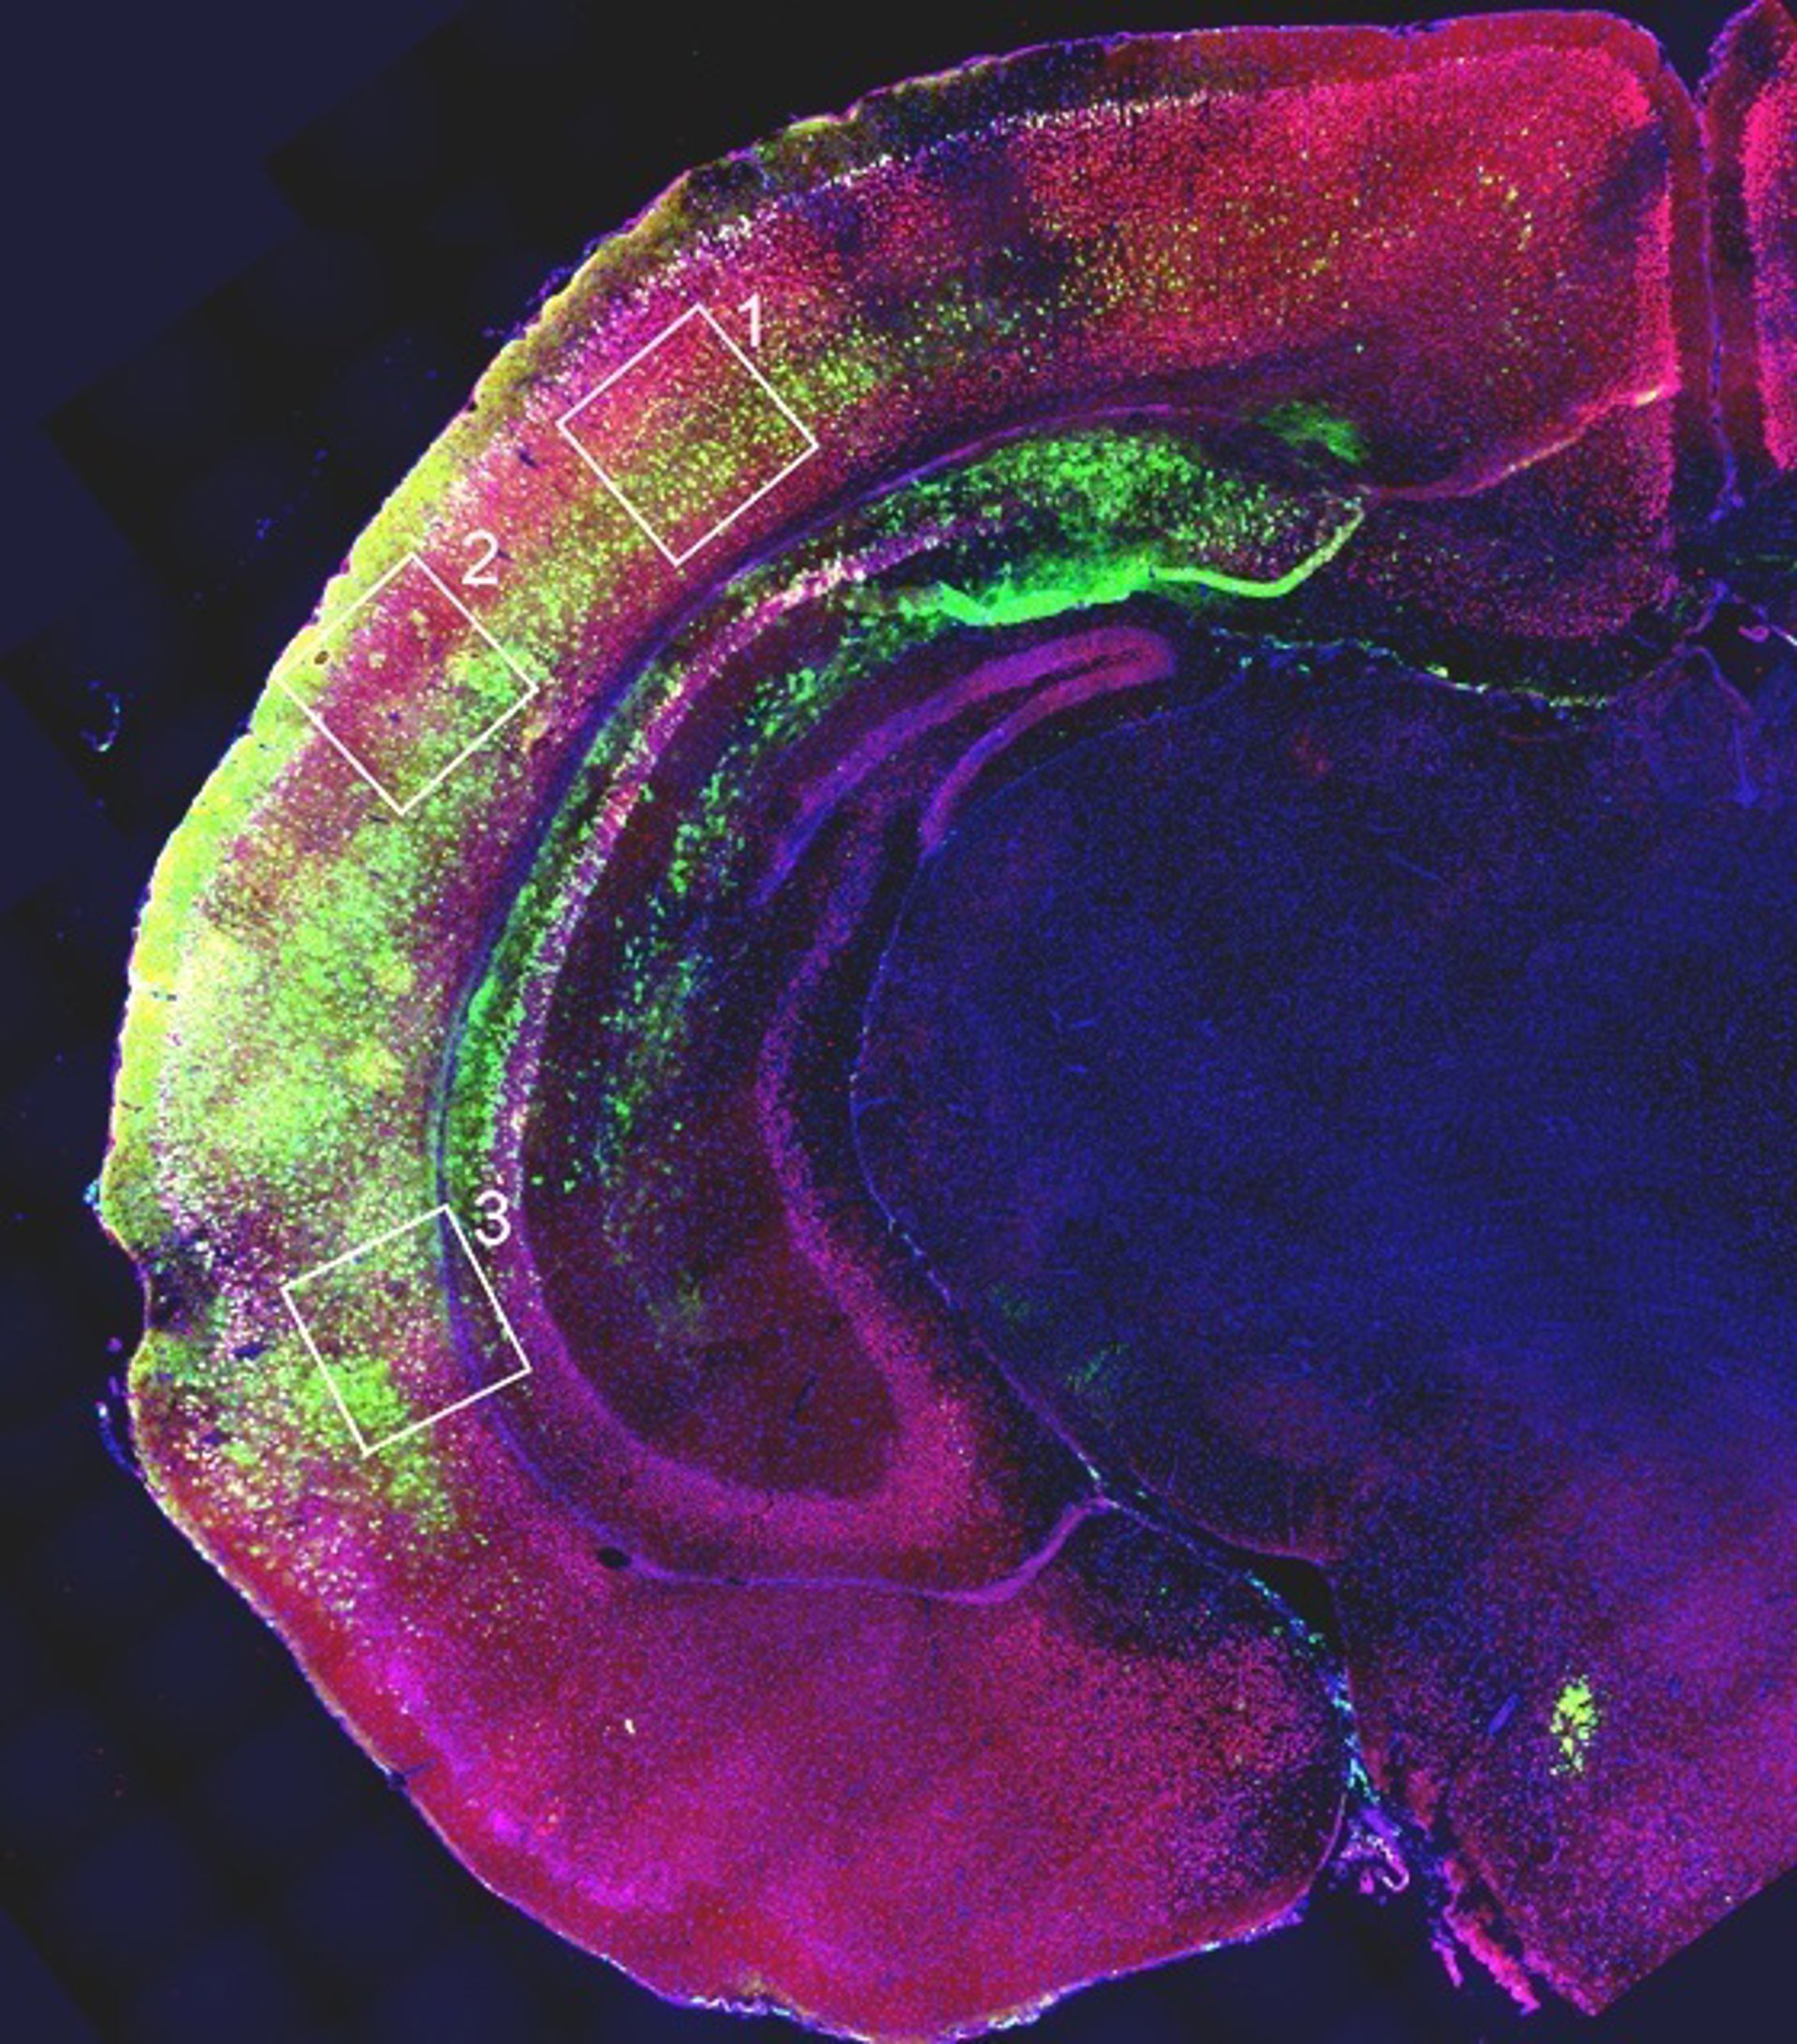

Estrategia contra el síndrome de Rett

SISSA